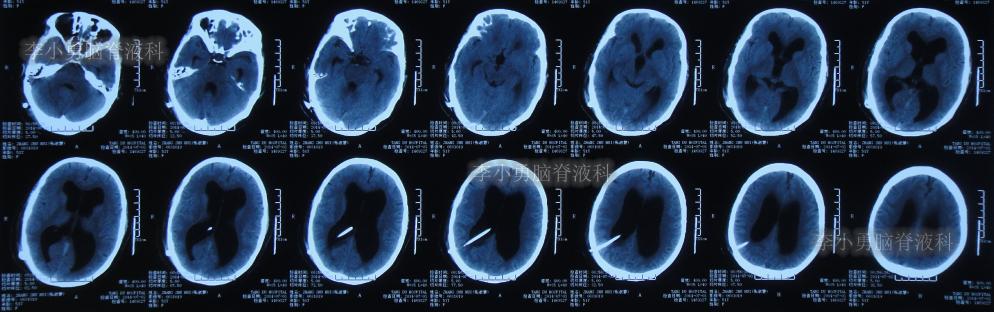

住院后第5天即2014年7月2日,进行了脑室腹腔分流术,术后次日即2014年7月3日查头颅CT:脑室分流术后状态( 图-4 )。

图-4: 2014年7月3日头颅CT

脑室腹腔分流术后第7天即2014年7月7日,查头颅CT:脑室仍然扩张( 图-5 )。

图-5: 2014年7月7日头颅CT